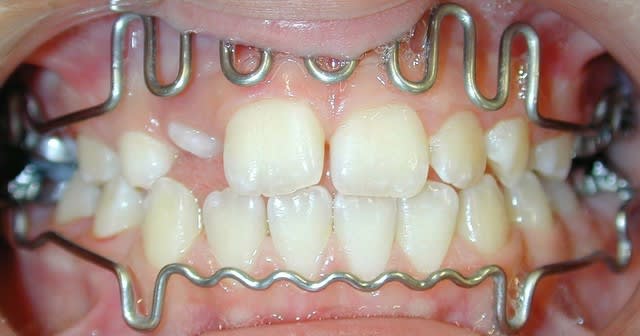

l'occlusion;

NB: Dans les 2 cas , pas de version des inc infs!

cas 2;Lea

BHG 9mois PUIS eln +2 LBs 15mois